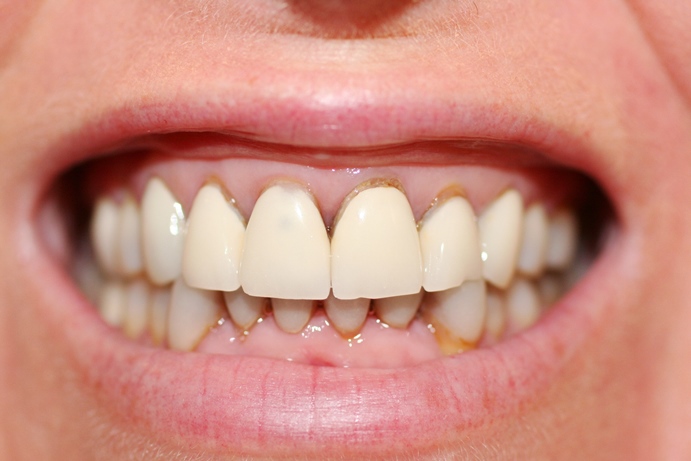

Giữa "ma trận" quảng cáo, việc chọn đúng nơi gửi gắm nụ cười là quyết định mang tính đầu tư cho tương lai. Một nha khoa uy tín không nhất thiết phải có giá đắt nhất, nhưng phải đảm bảo các tiêu chí vàng sau đây:

Hậu quả làm răng sứ giá rẻ